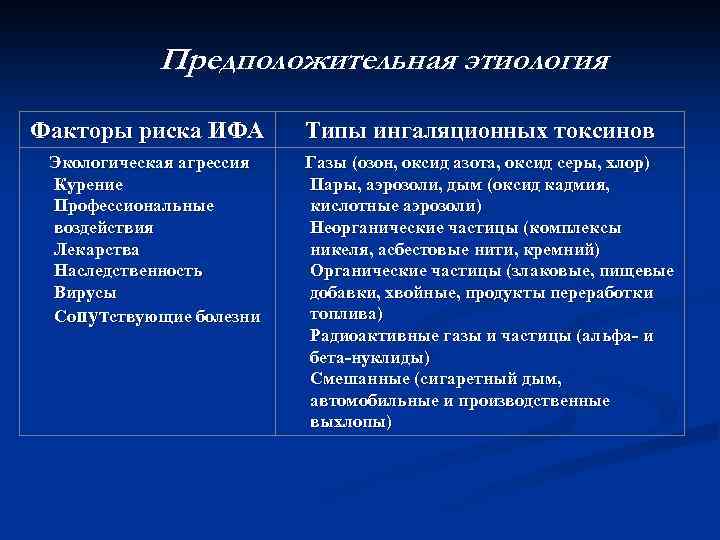

Предположительная этиология Факторы риска ИФА Экологическая агрессия Курение Профессиональные воздействия Лекарства Наследственность Вирусы Сопутствующие болезни Типы ингаляционных токсинов Газы (озон, оксид азота, оксид серы, хлор) Пары, аэрозоли, дым (оксид кадмия, кислотные аэрозоли) Неорганические частицы (комплексы никеля, асбестовые нити, кремний) Органические частицы (злаковые, пищевые добавки, хвойные, продукты переработки топлива) Радиоактивные газы и частицы (альфа- и бета-нуклиды) Смешанные (сигаретный дым, автомобильные и производственные выхлопы)